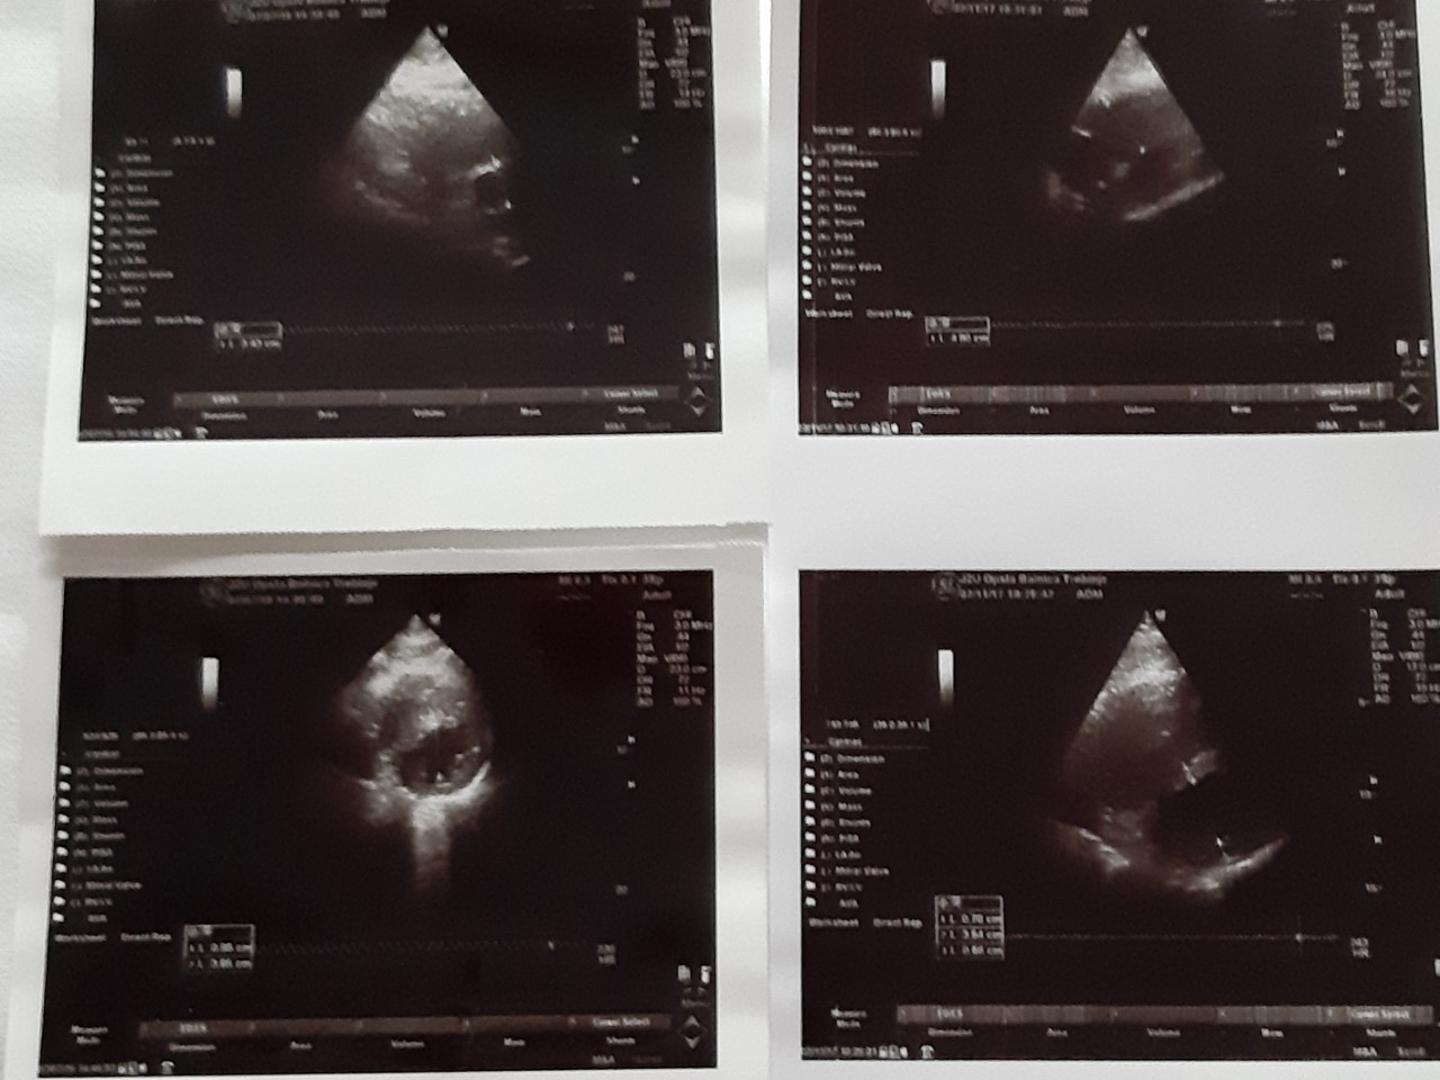

Aleksandar je specifičan po tome što njegovo srce, jetru i pluća nitko ne može primiti niti mu itko može donirati organe

Foto: Vecernji.ba